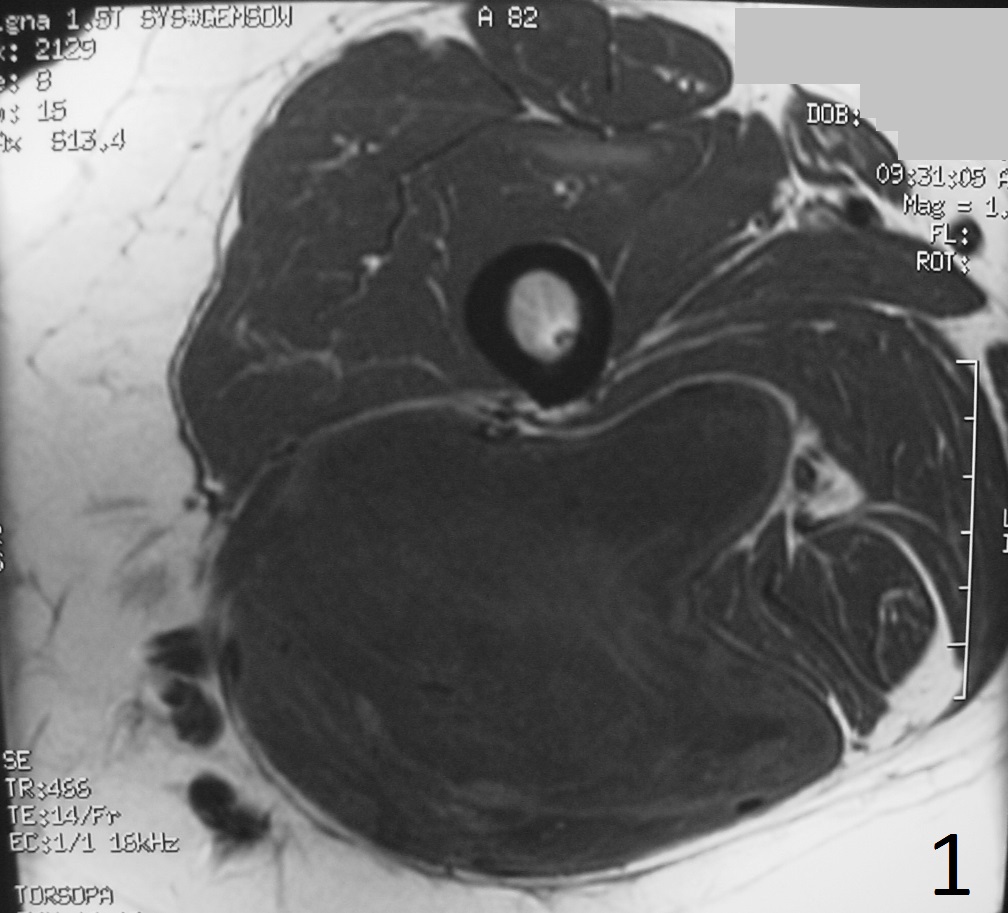

Fig. 1-2: The MRI of a solitary fibrous tumor is non specific. Any type of sarcoma can appear similar. Axial MRI of the thigh shows a well circumscribed and big lobulated mass low/intermediate signal on T1W (Fig. 1), enhancement on T1W FS post-gadolinium images with some areas of necrosis (Fig. 2).